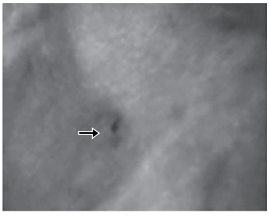

A figura seguinte mostra lesão decorrente de projétil de arma de fogo.

É correto afirmar que

É correto afirmar que